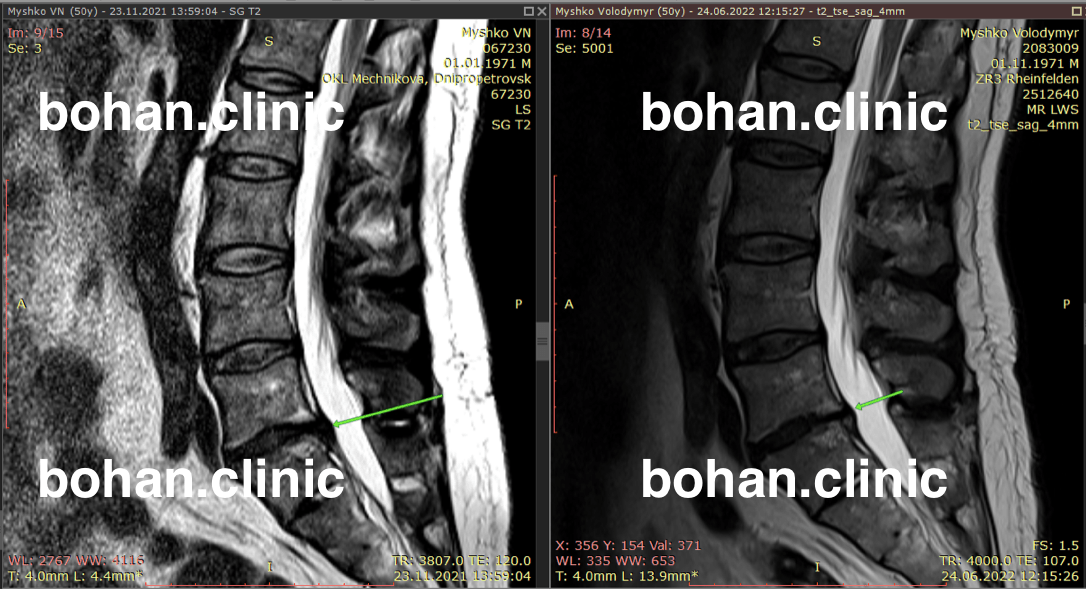

Метод лікування грижі шляхом стимуляції резорбції в Україні був впроваджений у 2020-2021 роках.  Алгоритм оцінки грижі на предмет резорбції, що використовується у клініках – є авторським, розроблений лікарем Боханом А.Ю.